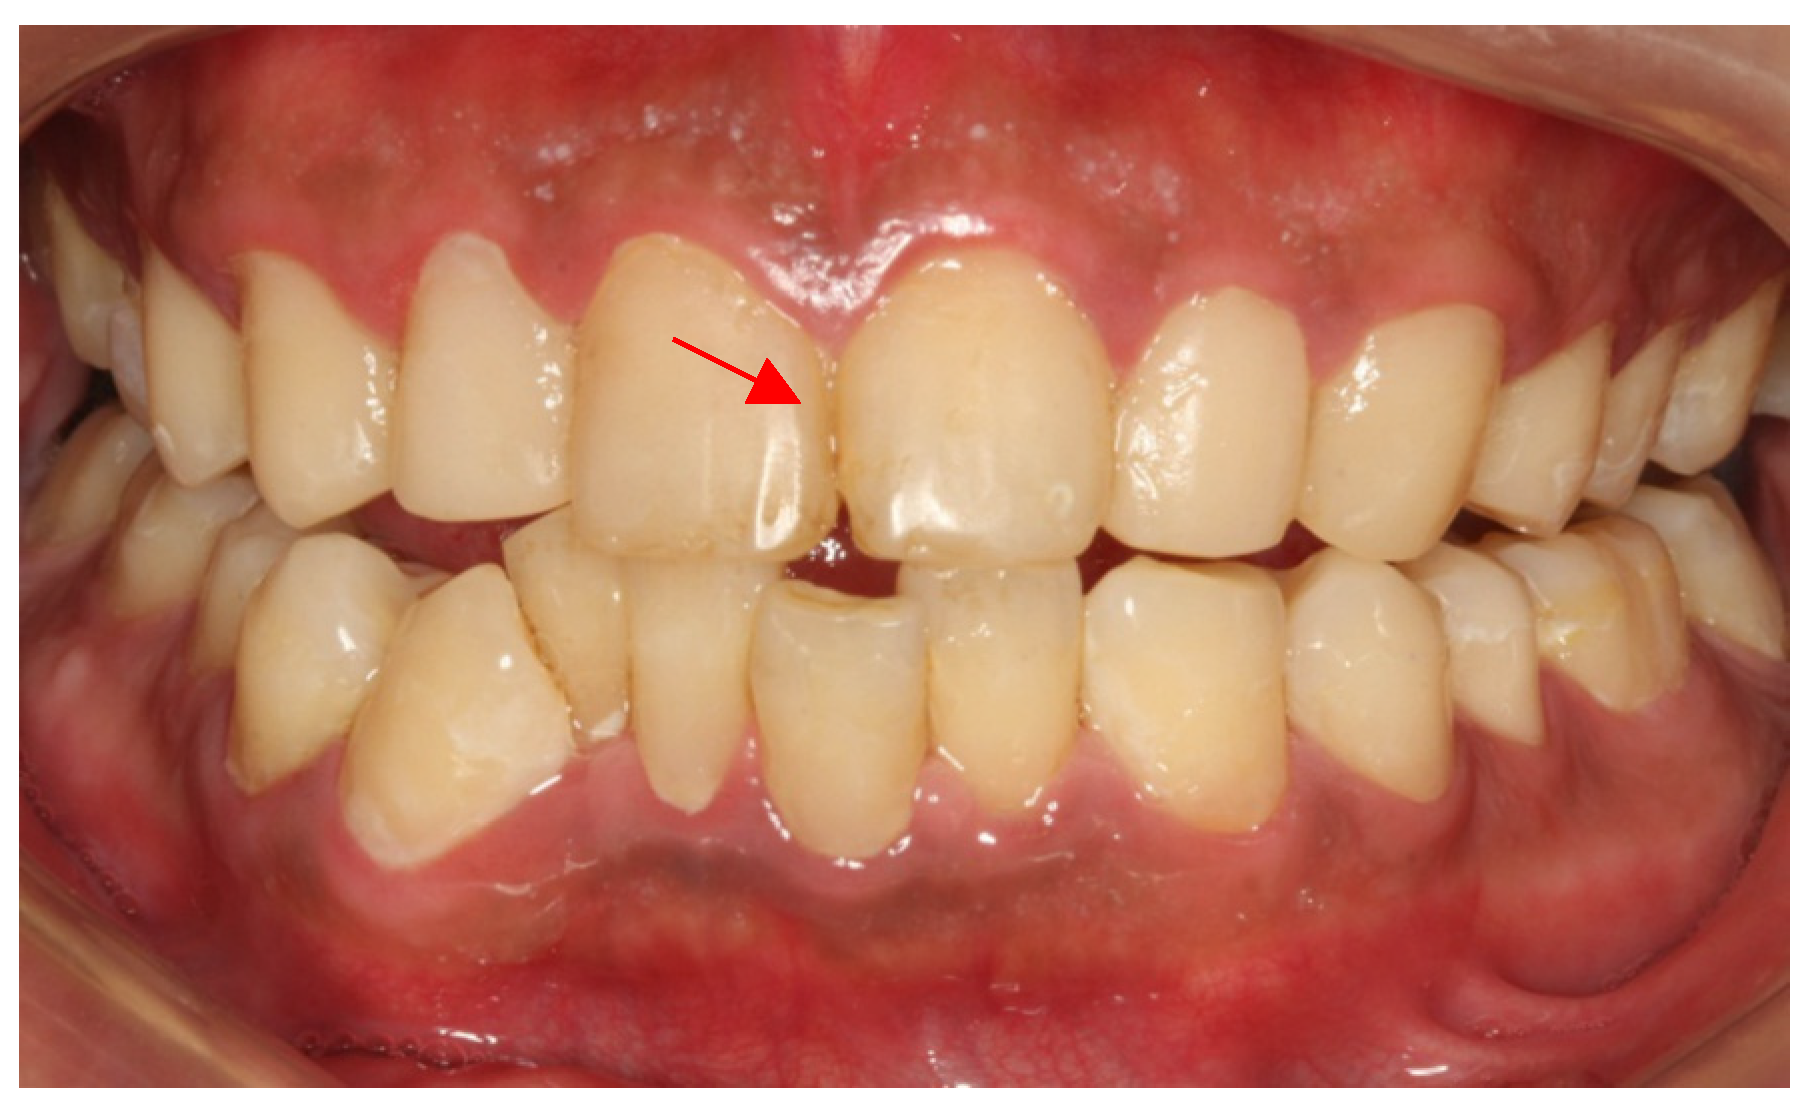

A 26-year-old male patient came to our clinic because of spontaneous pain in his right posterior tooth for one week. The patient had no systemic disease, and the family history showed no abnormalities. He described his job as a waiter with no exposure to acid substances. However, he loves to drink Coca-Cola and drinks more than 1 L of Coca-Cola every day; he also loves snacks and brushes his teeth less than once a day. These are the main causes of his dental caries. Dental examination found that the patient had poor dental hygiene with I-II° calculus supragingival and subgingival. All his teeth had extensive caries on the cervical region of the buccal and labial surfaces. The caries of teeth #14–24 even invades the tooth cusps. No lesions were found in the palatal and lingual surface. The pulpal surfaces of erosive lesions contained brown-colored, leathery, carious dentin. None of the pulp cavities were involved and the teeth remained asymptomatic on percussion, palpation and cold testing, except for tooth #46. The patient’s toothache came from tooth #46. There were two visible holes in teeth 46 buccal and occlusal surface, the perforation could be detected in the buccal surface, and the probing pain was obvious. There was no pain on percussion but severe pain on cold testing and heat testing (Figure 2a–d).

Figure 2.

(a) The photograph of the patient at first visit; (b) Upper teeth; (c) Lower teeth; (d) Panoramic X-ray of the patient (after the root canal therapy of teeth 46).